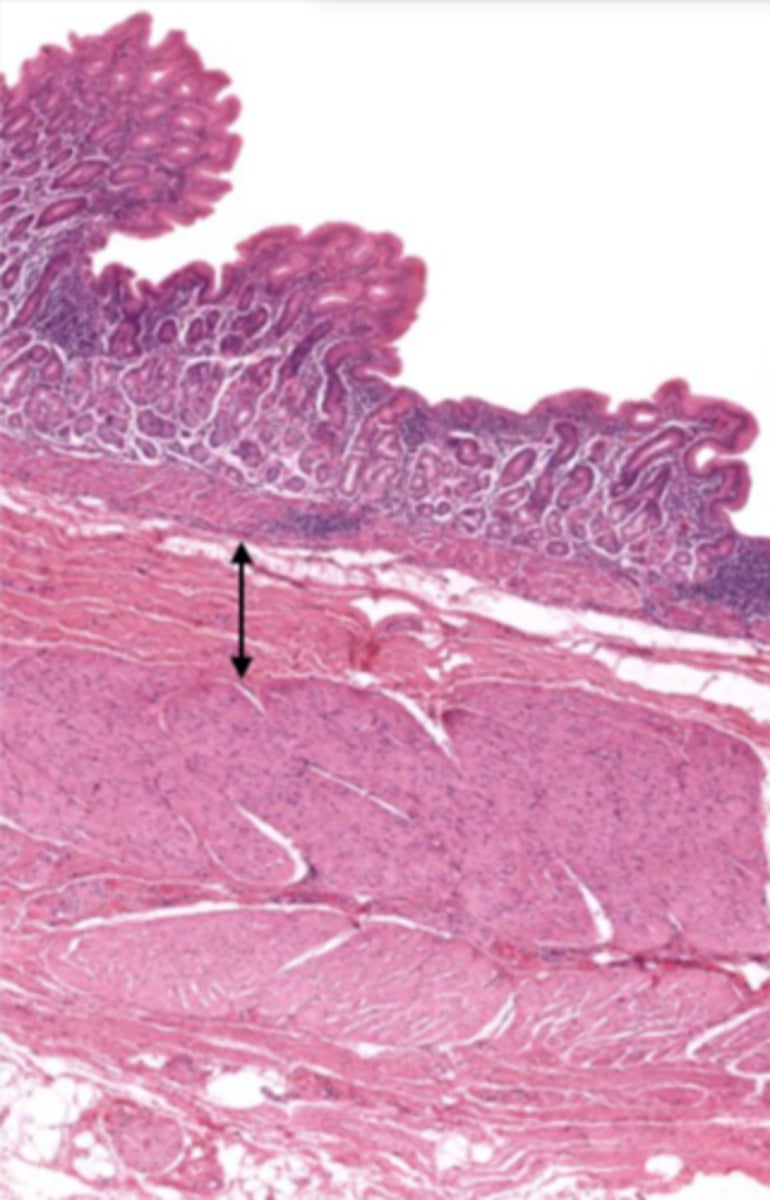

esophagus (histology)

lumen (esophagus)

mucosa (esophagus)

mucosal epithelium (esophagus)

stratified squamous epithelium

what kind of epithelium lines the mucosa of the esophagus?

lamina propria (esophagus)

muscularis mucosa (esophagus)

submucosa (esophagus)

contains glands and blood supply

muscularis externa (esophagus)

serosa/adventitia (esophagus)